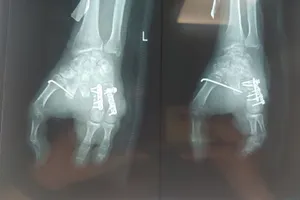

Theo đó, bệnh nhân NHP (sinh năm 2003) nhập viện lúc 20 giờ 51 ngày 5-1 trong tình trạng chấn thương đầu, gãy hở 1/3 dưới hai cẳng chân phải. Êkip điều trị đánh giá và chỉ định mổ cấp cứu ngay trong đêm. Bệnh nhân được cắt lọc vết thương chân phải và nẹp bột bất động xương gãy.

Ca mổ hoàn thành lúc 5 giờ sáng 6-1, hiện bệnh nhân ổn định, đang tiếp tục được theo dõi.